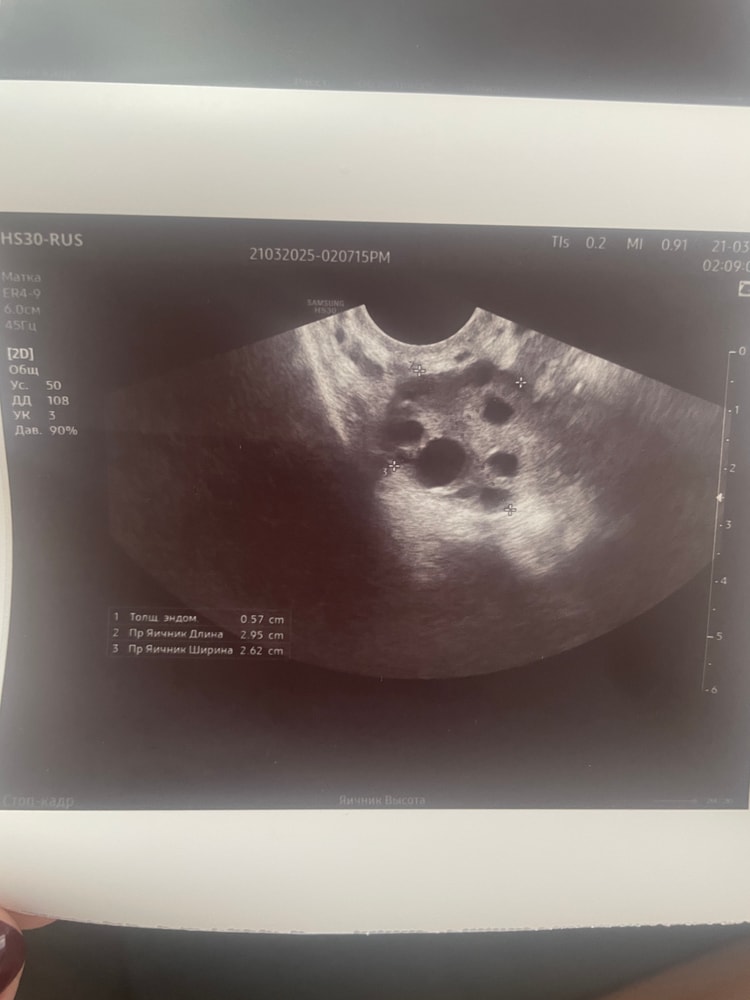

Девочки, узист написал нет дф, 15дц. Кто разбирается, посмотрите, пожалуйста, это просто фолликул крупный или все же доминантный?